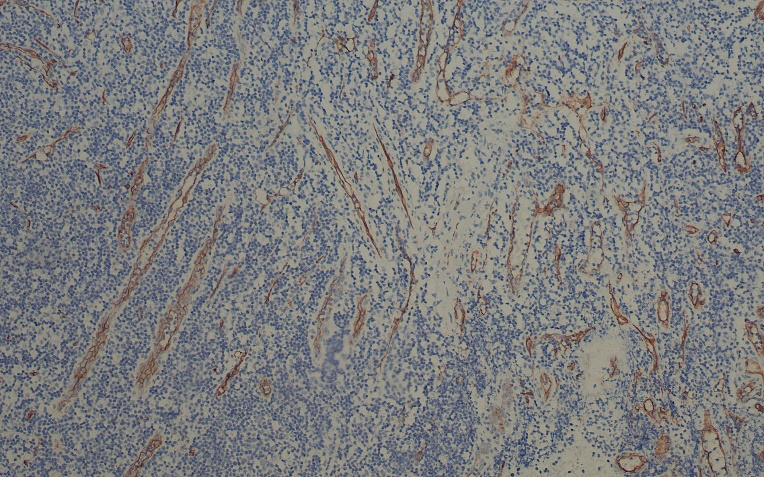

CD34

CD34是一种分子量为110kDa的单链膜糖蛋白,选择性的表达于人体造血髓系干细胞、淋巴系细胞、血管内皮细胞和部分急性白血病。在血管内皮细胞的表达中增生活跃的内皮细胞表达高于非增生期的内皮细胞。该抗体可用于良/恶性血管源性肿瘤的研究。

• CD34扁桃体